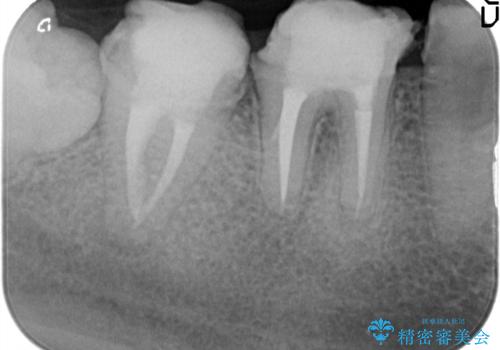

治療途中で長期間放置していたため、歯が歯ぐきから挺出(伸びてくる)してしまい、十分に強度を担保できるセラミッククラウンを装着するスペースが不足した状態です。

加えて、舌の邪魔になっている骨隆起や根尖病変といった問題を歯周外科・精密根管治療を行い、しっかりとスペースを確保したのちセラミッククラウンを作製していきます。